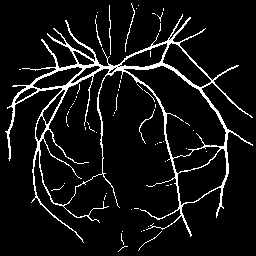

Synthetic Data Samples

Figure: Synthetic data generated by StyleGAN2-ADA for ACDC (top) and FIVES (bottom) datasets. Left to right: first 3 are original images, next 3 generated using 5% real data, last 3 using 10% real data.